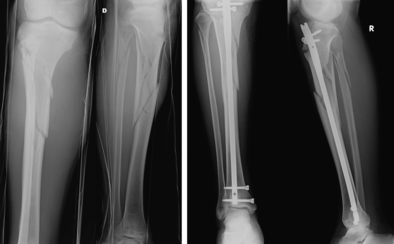

Caso Clinico 1 Frattura Prossimale Tibia E Perone Ao 42c1 Download Scientific Diagram

Figure 6 Il Trattamento Con Chiodo Delle Fratture Del Terzo Prossimale Di Tibia Springerlink

Frattura Di Gamba Tecnica Percutanea Mipo